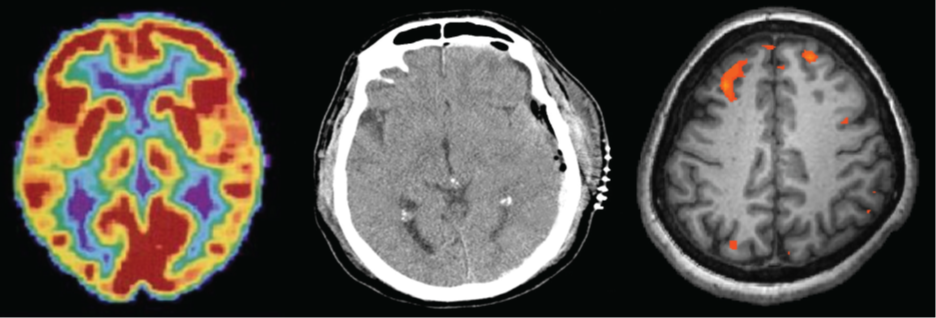

Three brain-imaging scans are shown.

Figure 3.1 Different brain imaging techniques provide scientists with insight into different aspects of how the human brain functions. Left to right, PET scan (positron emission tomography), CT scan (computerized tomography), and fMRI (functional magnetic resonance imaging) are three types of scans. (credit “left”: modification of work by Health and Human Services Department, National Institutes of Health; credit “center”: modification of work by “Aceofhearts1968″/Wikimedia Commons; credit “right”: modification of work by Kim J, Matthews NL, Park S.)

Positron emission tomography (PET) scans create pictures of the living, active brain (Figure 3.30). An individual receiving a PET scan drinks or is injected with a mildly radioactive substance, called a tracer. Once in the bloodstream, the amount of tracer in any given region of the brain can be monitored. As a brain area becomes more active, more blood flows to that area. A computer monitors the movement of the tracer and creates a rough map of active and inactive areas of the brain during a given behavior. PET scans show little detail, are unable to pinpoint events precisely in time, and require that the brain be exposed to radiation; therefore, this technique has been replaced by the fMRI as an alternative diagnostic tool. However, combined with CT, PET technology is still being used in certain contexts. For example, CT/PET scans allow better imaging of the activity of neurotransmitter receptors and open new avenues in schizophrenia research. In this hybrid CT/PET technology, CT contributes clear images of brain structures, while PET shows the brain’s activity.

A brain scan shows different parts of the brain in different colors.

Figure 3.30 A PET scan is helpful for showing activity in different parts of the brain. (credit: Health and Human Services Department, National Institutes of Health)

In magnetic resonance imaging (MRI), a person is placed inside a machine that generates a strong magnetic field. The magnetic field causes the hydrogen atoms in the body’s cells to move. When the magnetic field is turned off, the hydrogen atoms emit electromagnetic signals as they return to their original positions. Tissues of different densities give off different signals, which a computer interprets and displays on a monitor. Functional magnetic resonance imaging (fMRI) operates on the same principles, but it shows changes in brain activity over time by tracking blood flow and oxygen levels. The fMRI provides more detailed images of the brain’s structure, as well as better accuracy in time, than is possible in PET scans (Figure 3.31). With their high level of detail, MRI and fMRI are often used to compare the brains of healthy individuals to the brains of individuals diagnosed with psychological disorders. This comparison helps determine what structural and functional differences exist between these populations.

A brain scan shows brain tissue in gray with some small areas highlighted red.

Figure 3.31 An fMRI shows activity in the brain over time. This image represents a single frame from an fMRI. (credit: modification of work by Kim J, Matthews NL, Park S.)